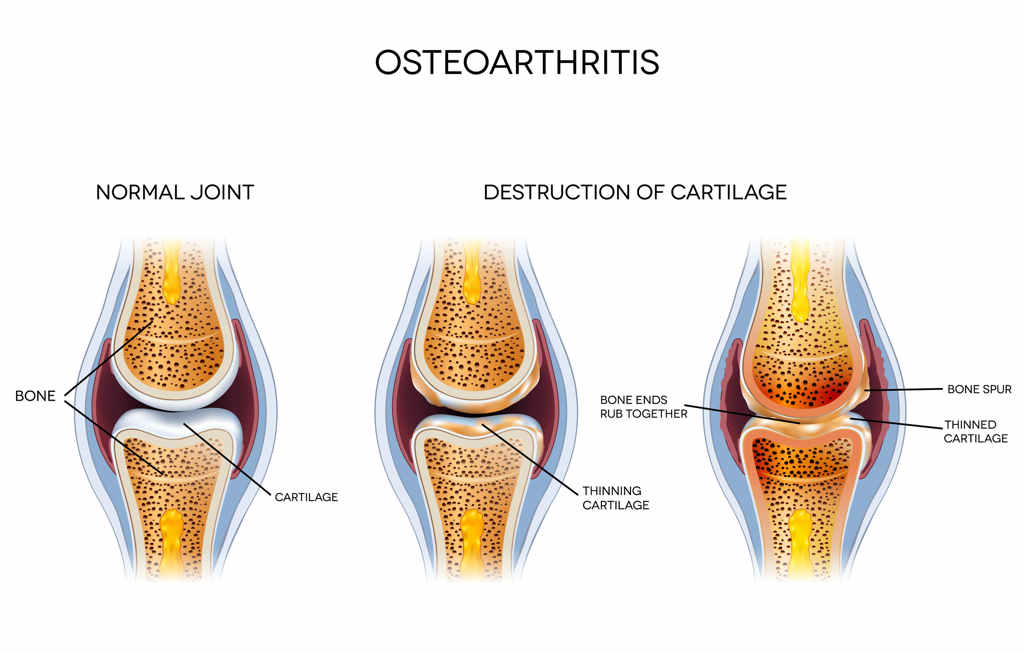

Die Kniearthrose ist eine degenerative Veränderung des Knorpels im Kniegelenk, also kurz ein Knorpelschaden. Umgangssprachlich sagt man auch Verschleiß. Die Ursachen einer Arthrose sind immer noch nicht ausreichend erforscht, wobei natürlich auch eine Überlastung oder eine Verletzung im Einzelfall eine gewichtige Rolle spielen kann. Ich denke hier an bestimmte Sportarten, Unfälle oder auch starkes Übergewicht.

Man teilt die Schwere einer Arthrose in 4 Grade auf, Grad I ist eine Aufrauhung der Knorpeloberfläche. Grad II Grad III Grad IV.